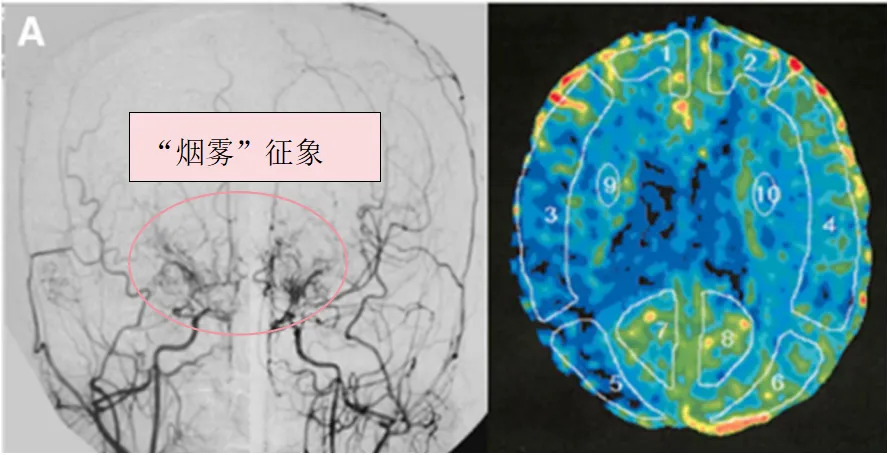

术前血管造影(双侧颈总动脉正位图)显示双侧颈内动脉末端有“烟雾血管狭窄征象”,双侧大脑中动脉(MCA)狭窄(左)。术前Xe-CT显示双侧MCA区域脑血流减少(右:15.9,左:22.8 ml/100 g/min)(右)。